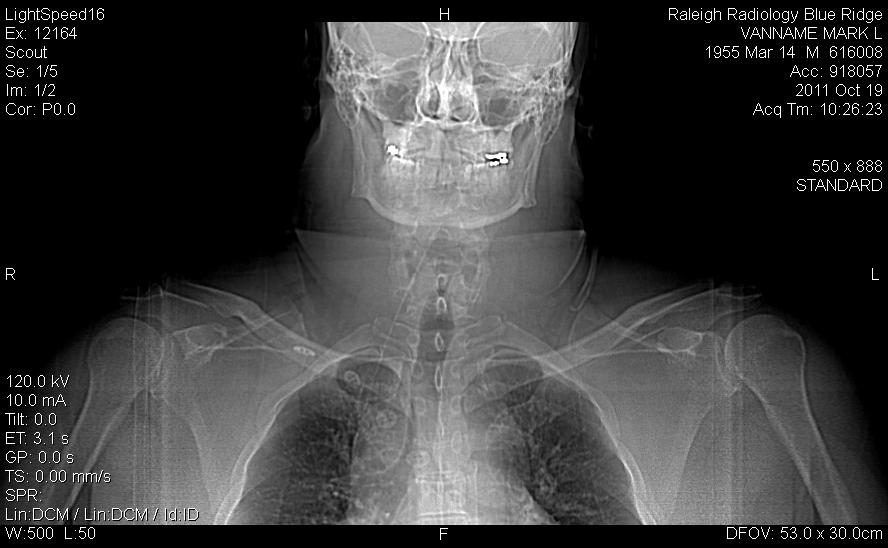

It's pretty cool stuff. Here's the first shot, my head straight on.

Do I look like the Terminator, or what?

Yeah, yeah, go ahead and say it: damn, that's a big neck. Yes, it is.